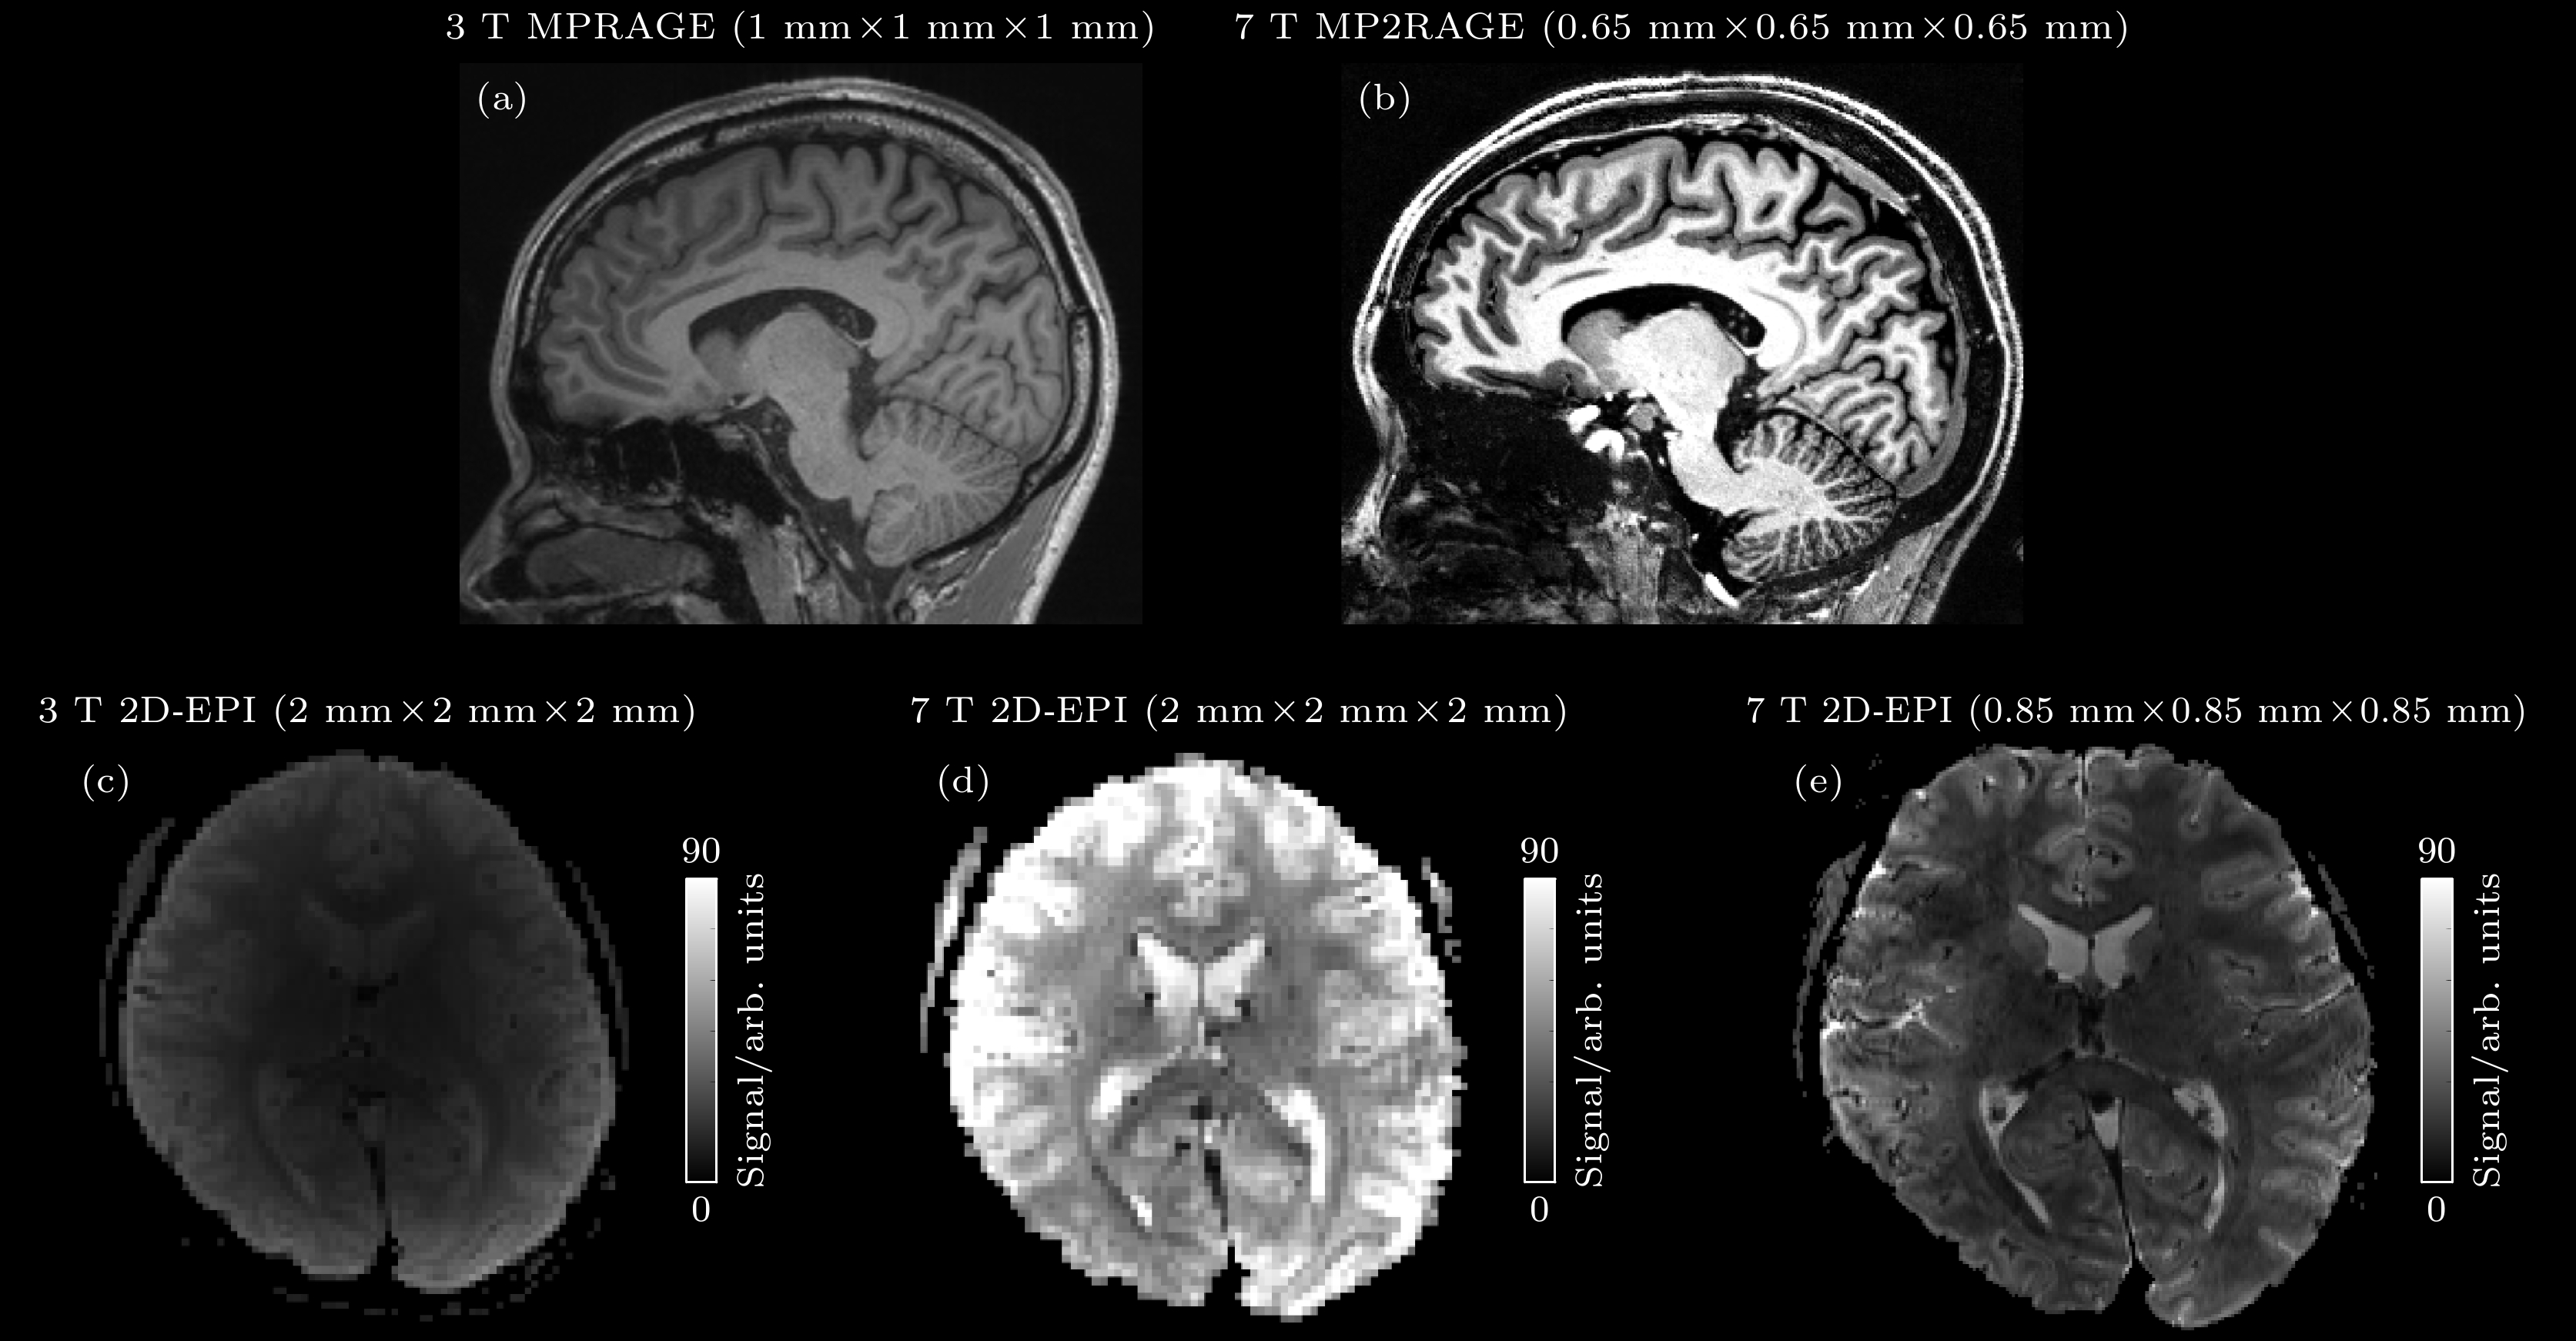

超高场磁共振成像(ultra-high field magnetic resonance imaging, UHF-MRI)是主磁场强度为7 T及以上磁共振成像的统称. 与传统磁共振成像相比, UHF-MRI具有更高的信噪比和对比度. 因此, 在临床医学及神经科学等领域, 该技术的运用能够显著提高信号的探测灵敏度和图像的空间分辨率, 从而提供更丰富的生理病理信息. 目前, UHF-MRI在大脑功能和代谢成像两个方面发挥了重要的作用. 在脑功能研究方面, 高分辨率的皮层功能柱和分层成像有助于揭示神经信息流的方向; 在脑代谢研究中, 氢核与多核的波谱及成像技术提供了更精确的代谢信息, 有望在功能性和代谢性疾病的病理研究中取得重要突破. 本文介绍了UHF-MRI的发展历史和理论基础, 梳理了其关键优势及在脑功能和代谢成像应用研究中的现状, 总结了当前面临的挑战, 并提出了未来重点研究方向.Magnetic resonance imaging (MRI) is one of the most important imaging modalities used in contemporary clinical radiology research and diagnostic practice due to its non-invasive nature, absence of ionizing radiation, high soft tissue contrast, and diverse imaging capabilities. Nevertheless, traditional MRI systems are limited by a relatively low signal-to-noise ratio (SNR), which can be enhanced by increasing the strength of the main magnetic field. Ultra-high field MRI (UHF-MRI) typically refers to MRI systems with a main magnetic field strength of 7 T or higher. The UHF-MRI improves image SNR and extends the boundaries of spatial resolution and detection sensitivity. These advancements not only provide clinicians with richer and more accurate physiological and pathological information but also open new avenues for research on life sciences and cognitive neuroscience. Currently, the UHF-MRI plays a pivotal role in brain functional and metabolic imaging. In the brain function research, the implementation of high-resolution mesoscale functional imaging techniques has enabled the investigation of laminar-specific neuronal activity within cortical layers, including feedforward and feedback neural information processing pathways. In metabolic studies, the application of hydrogen and multi-nuclear spectroscopy and imaging has yielded more accurate metabolic data, thereby holding substantial promise for advancing our understanding of the pathophysiology underlying functional and metabolic diseases. However, the UHF-MRI is also subject to certain limitations, including issues related to radio-frequency (RF) field in homogeneity, elevated specific absorption ratio (SAR), and susceptibility artifacts. In this paper, the historical evolution and theoretical underpinnings of UHF-MRI are reviewed, its principal advantages over low-field MRI is elucidated, and the contemporary research on UHF-MRI applications in human brain function and metabolic imaging research are integrated together. Furthermore, the technical limitations associated with UHF-MRI implementation are critically examined and the potential avenues are proposed for the future research direction. [1] [2] [3] [4] [5] [6] [7] [8] [9] [10] [11] [12] [13] [14] [15] [16] [17] [18] [19] [20] [21] [22] [23] [24] [25] [26] [27] [28] [29] [30] [31] [32] [33] [34] [35] [36] [37] [38] [39] [40] [41] [42] [43] [44] [45] [46] [47] [48] [49] [50] [51] [52] [53] [54] [55] [56] [57] [58] [59] [60] [61] [62] [63] [64] [65] [66] [67] [68] [69] [70] [71] [72] [73] [74] [75] [76] [77] [78] [79] [80] [81] [82] [83] [84] [85] [86] [87] [88] [89] [90] [91] [92] [93] [94] [95] [96] [97] [98] [99] [100] [101] [102] [103] [104] [105] [106] [107] [108] [109] [110] [111] [112] [113] [114] [115] [116] [117] [118] [119] [120] [121] [122] [123] [124] [125] [126] [127] [128] [129] [130] [131] [132] [133] [134] [135] [136] [137] [138] [139] [140] [141] [142] [143] [144] [145] [146] [147] [148] [149] [150] [151] [152] [153] [154] [155] [156] [157] [158] [159] [160] [161] [162] [163] [164] [165] [166] [167] [168] [169] [170] [171] [172] [173] [174] [175] [176] [177] [178] [179] [180] [181] [182] [183] [184] [185] [186] [187] [188] [189] [190] [191] [192] [193] [194] [195] [196] [197] [198] [199] [200]